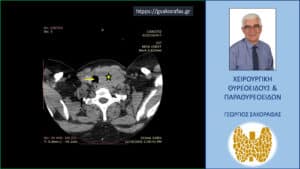

Αξονική τομογραφία – εγκάρσια διατομή στο ύψος του τραχήλου. Ο ευμεγέθης όζος (κίτρινος αστερίσκος) που απωθεί την τραχεία προς τα αριστερά (κίτρινο βέλος).